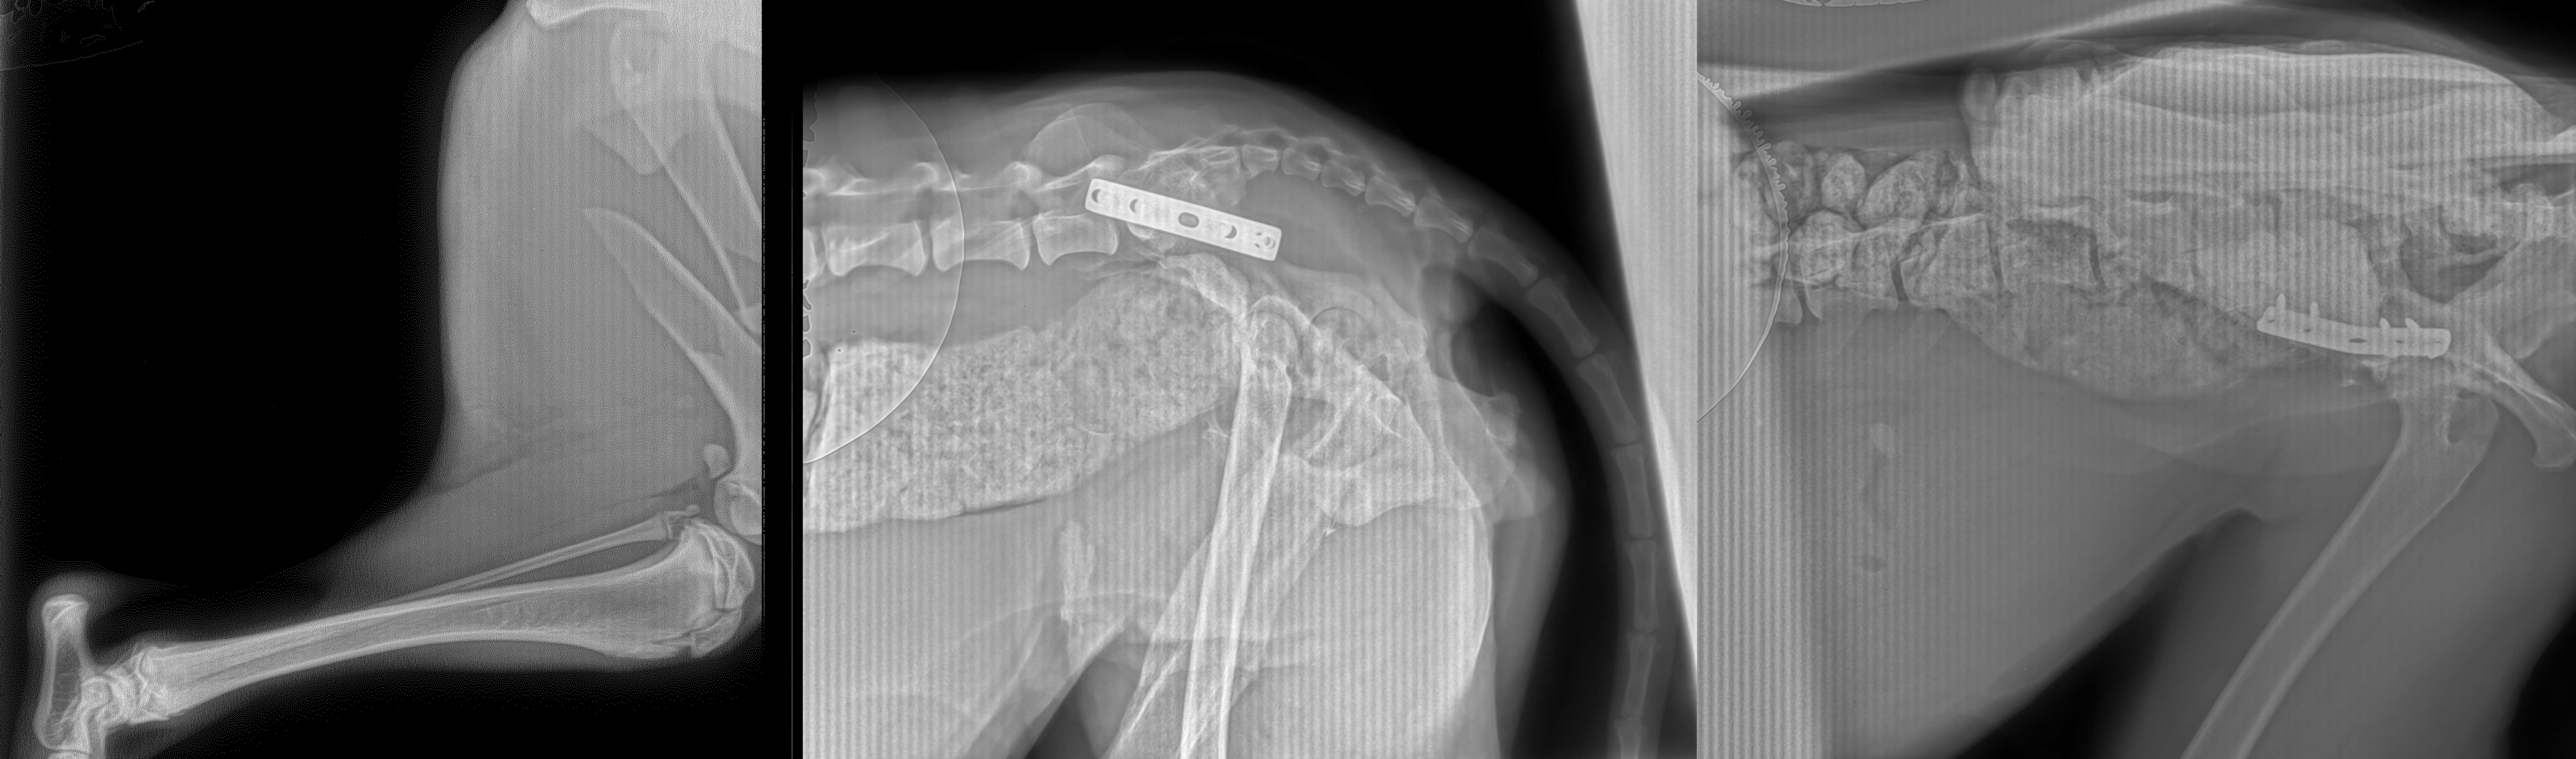

Ortopedia

La ortopedia es una especialidad dedicada a corregir daños al sistema esquelético, músculos y ligamentos, y evitar deformaciones o traumas en estos.

Algunos ejemplos de procedimientos ortopédicos que realiza Wild Life Care incluyen:

Reparación de fracturas óseas

Fijaciones externas